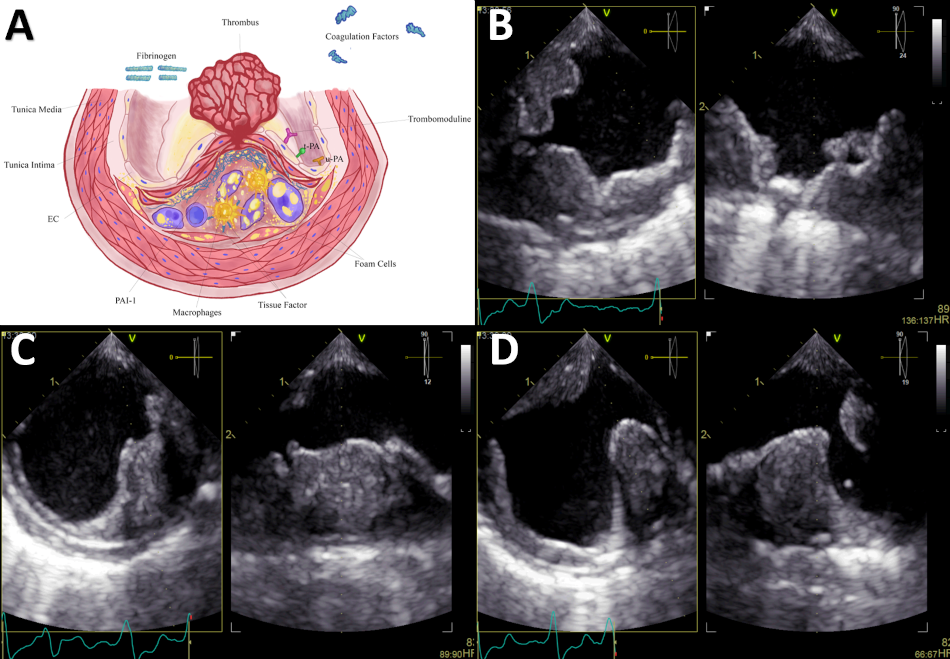

Figure. 3

A. After rupture of the fibrous cap, coagulation molecules from the bloodstream come into contact with foam cells, tissue factor, and microparticles derived from apoptotic atheroma cells, triggering thrombus formation in the ruptured plaque. The thrombotic equilibrium will determine whether plaque rupture will culminate in the formation of a persistent, distant-migrating thrombus or in its dissolution. B. TEE - Proximal third of the descending aorta. Orthogonal images showing extensive mural thrombotic formation of irregular border that occupies up to one third of the arterial lumen, with small movable elements on its surface in the long axis. C. TEE - Middle third of the descending aorta. Orthogonal images showing crescent-shaped thrombus in the short-axis view. D. TEE - Distal third of the descending aorta. Orthogonal images of wedge-shaped thrombus. Secondary thrombotic elements in opposite position to the initial one.

EC: endothelial cell; PAI-1: type 1 plasminogen activator inhibitor; TEE: transesophageal echocardiography; t-PA: tissue-type plasminogen activator; u-PA: urokinase-type plasminogen activator.